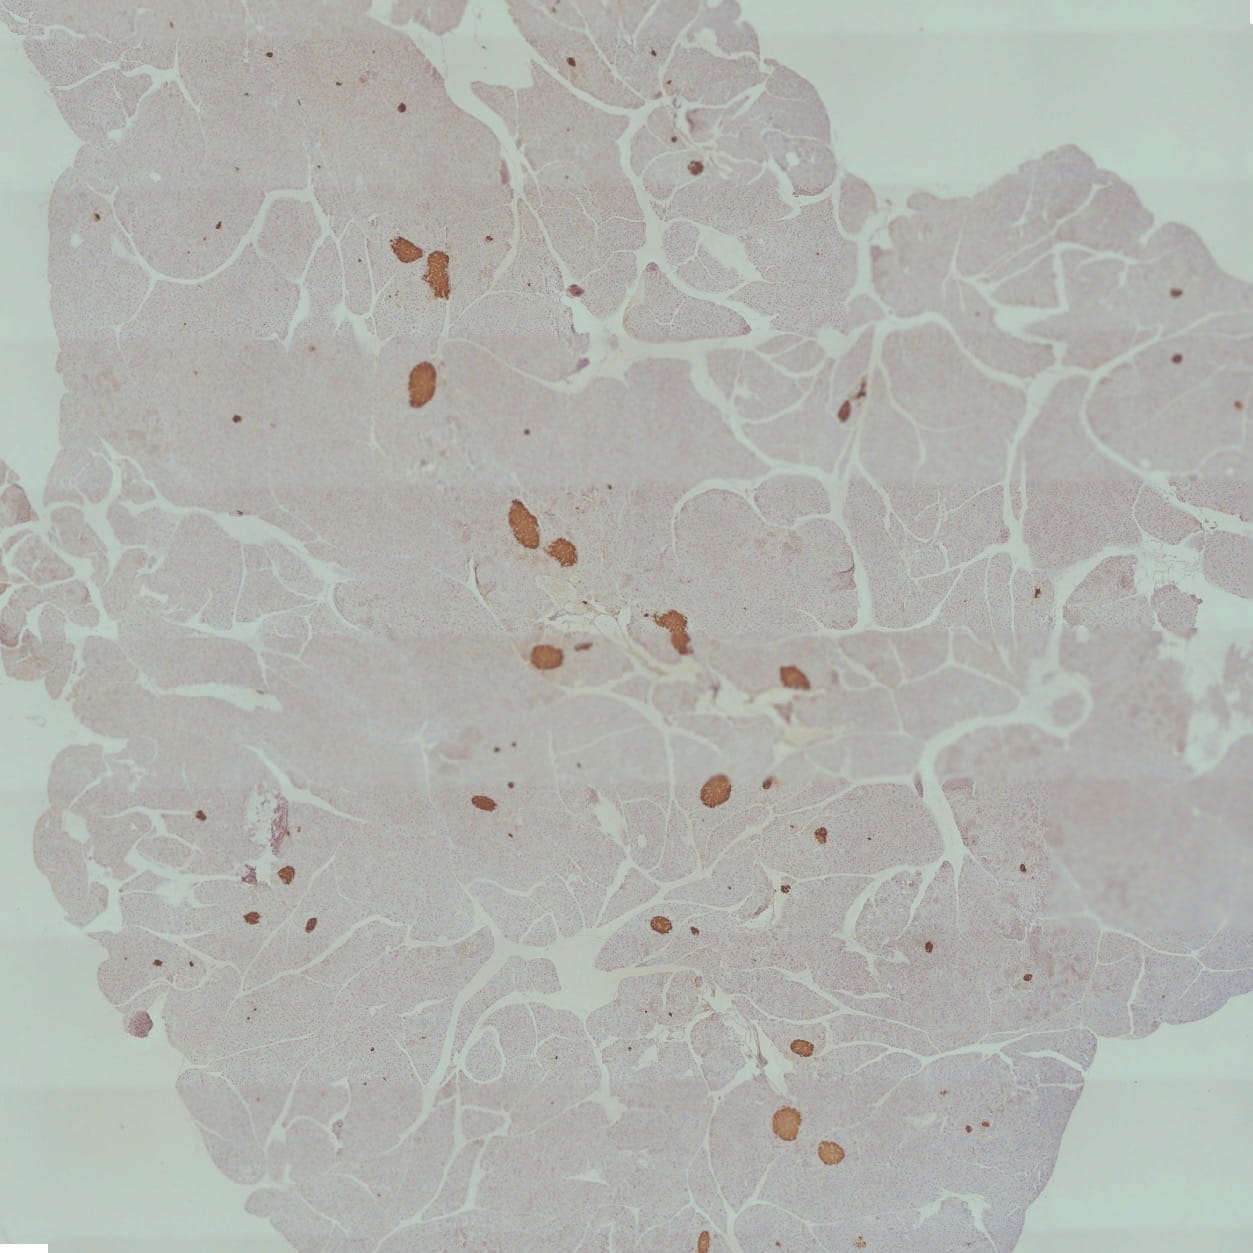

An image taken from a microscope. To answer that, Kono and his team looked at pancreatic beta cells—the ones responsible for insulin production, in vitro. Their data showed that exposure to cigarette smoke led to an imbalance of free radicals and antioxidants within the beta cells. That imbalance is called oxidative stress, which is correlated with increased ceramide content in the pancreas, reduced beta cell mass and depleted insulin production—just like they observed in the animal models.

(Pictured left: Paraffin section of pancreas tissue from mouse exposed to cigarette smoke. Immunostaining analysis revealed that the insulin-producing cells--shown as red/brown spots--were dramatically reduced by the cigarette smoke exposure.)